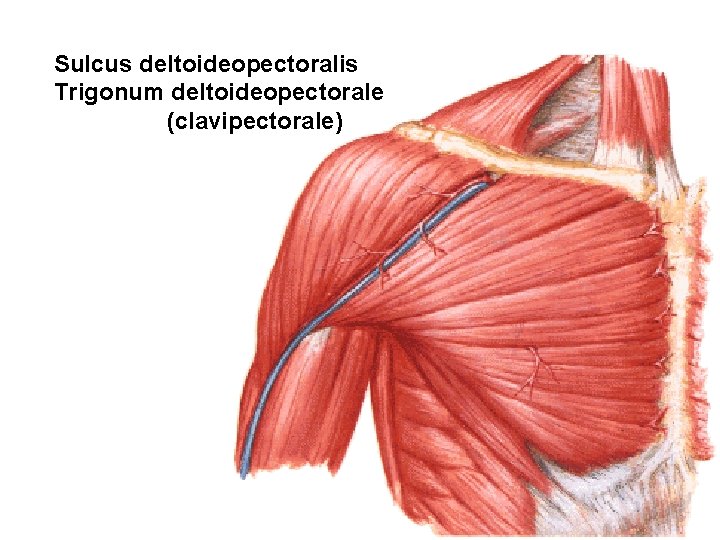

Sulcus deltoideopectoralis Trigonum deltoideopectorale (clavipectorale)